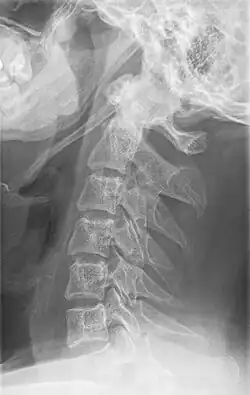

CT scan, coronal section showing bilateral extended styloid process and stylohyoid ligament ossification (incidental finding) -

Diagnosis is suspected when a patient presents with the symptoms of the classic form of "Eagle syndrome" e.g. unilateral neck pain, sore throat or tinnitus. Sometimes the tip of the styloid process is palpable in the back of the throat. The diagnosis of the vascular type is more difficult and requires an expert opinion. One should have a high level of suspicion when neurological symptoms occur upon head rotation. Symptoms tend to be worsened on bimanual palpation of the styloid through the tonsillar bed. They may be relieved by infiltration of lidocaine into the tonsillar bed. Because of the proximity of several large vascular structures in this area this procedure should not be considered to be risk free.

Imaging is important and is diagnostic. Visualizing the styloid process on a CT scan with 3D reconstruction is the suggested imaging technique.[13] The enlarged styloid may be visible on an orthopantogram or a lateral soft tissue X ray of the neck.